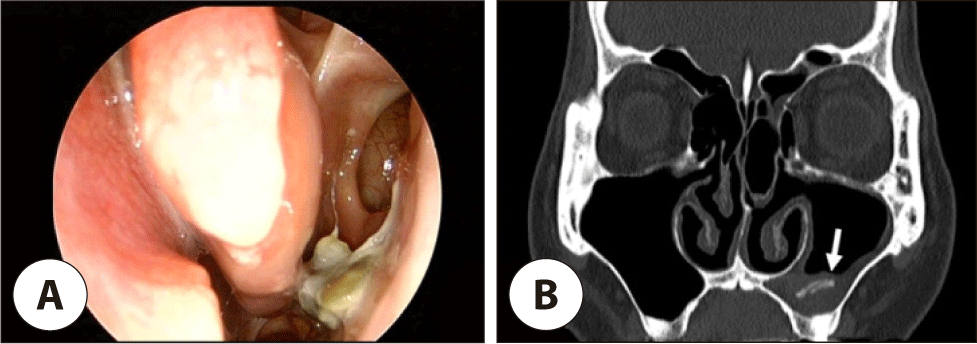

수술 5년 경과 후, 환자는 외래에 내원하였는데 그 동안 병원에서의 코로나 감염 우려로 오지 못했다고 하였다. 환자는 좌측 농성 비루와 후비루 증상이 호전되지 않는다고 하여 당일 CT를 시행하였는데 좌측 상악동에 부분적인 혼탁과 석회화 소견이 보였다(Fig. 3). 외래에서 수 차례 좌측 상악동 세척을 하였는데 환자의 좌측 중비도에서 단단하고 황색을 띠는 솜 형태의 여러 조각들이 관찰되며, 이는 섬세한 섬유성 조직과 얽혀 있었다(Fig. 4). 환자의 중비도에서 발견된 미세한 섬유조직은 수술 당시 사용한 Algi-pack®의 성분과 같은 것으로 생각되었다. 상악동 이물 제거 후 70도 내시경과 Water 영상에서 좌측 상악동에서 특이 소견이 관찰되지 않았다(Fig. 5). 이후 환자는 더 이상의 불편 증상을 호소하지 않았고 재발이나 합병증 없이 외래 추적 관찰 중이다.

jcohns-36-2-54-g4

Fig. 4. Endoscopic findings after maxillary sinus irrigations. (A), (B) multiple firm, yellowish, cotton-like fragments (arrow) are observed in the left middle meatus of the patient, entangled with delicate fibrous tissues (arrowhead).

jcohns-36-2-54-g5

Fig. 5. Endoscopic and radiographic findings after mass removal. (A) endoscopic view using a 70-degree endoscope shows a clear maxillary sinus. (B) water’s view radiograph shows no abnormal findings following removal of the left maxillary sinus mass.